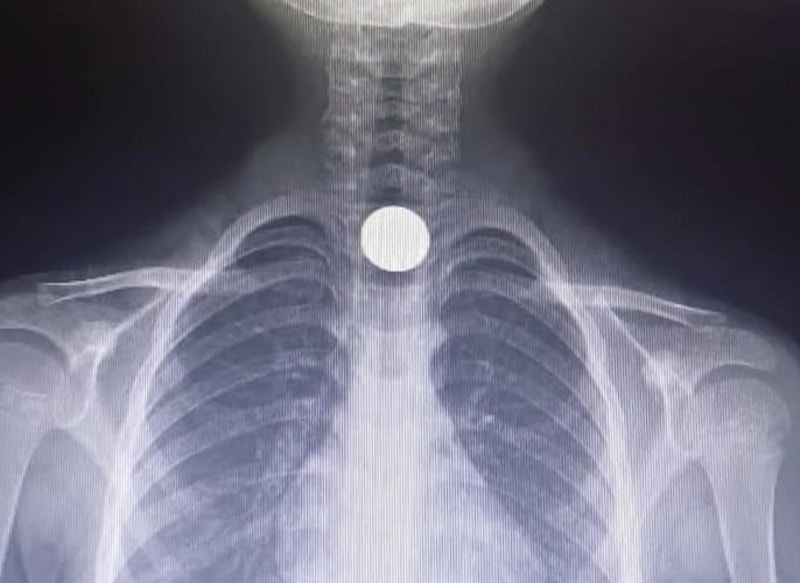

Hastanede yapılan tetkiklerde, küçük çocuğun yemek borusuna 50 kuruşluk madeni para kaçtığı tespit edildi.

Yusuf Z.'nin yemek borusundaki para, burada yapılan başarılı ameliyatla çıkartıldı.